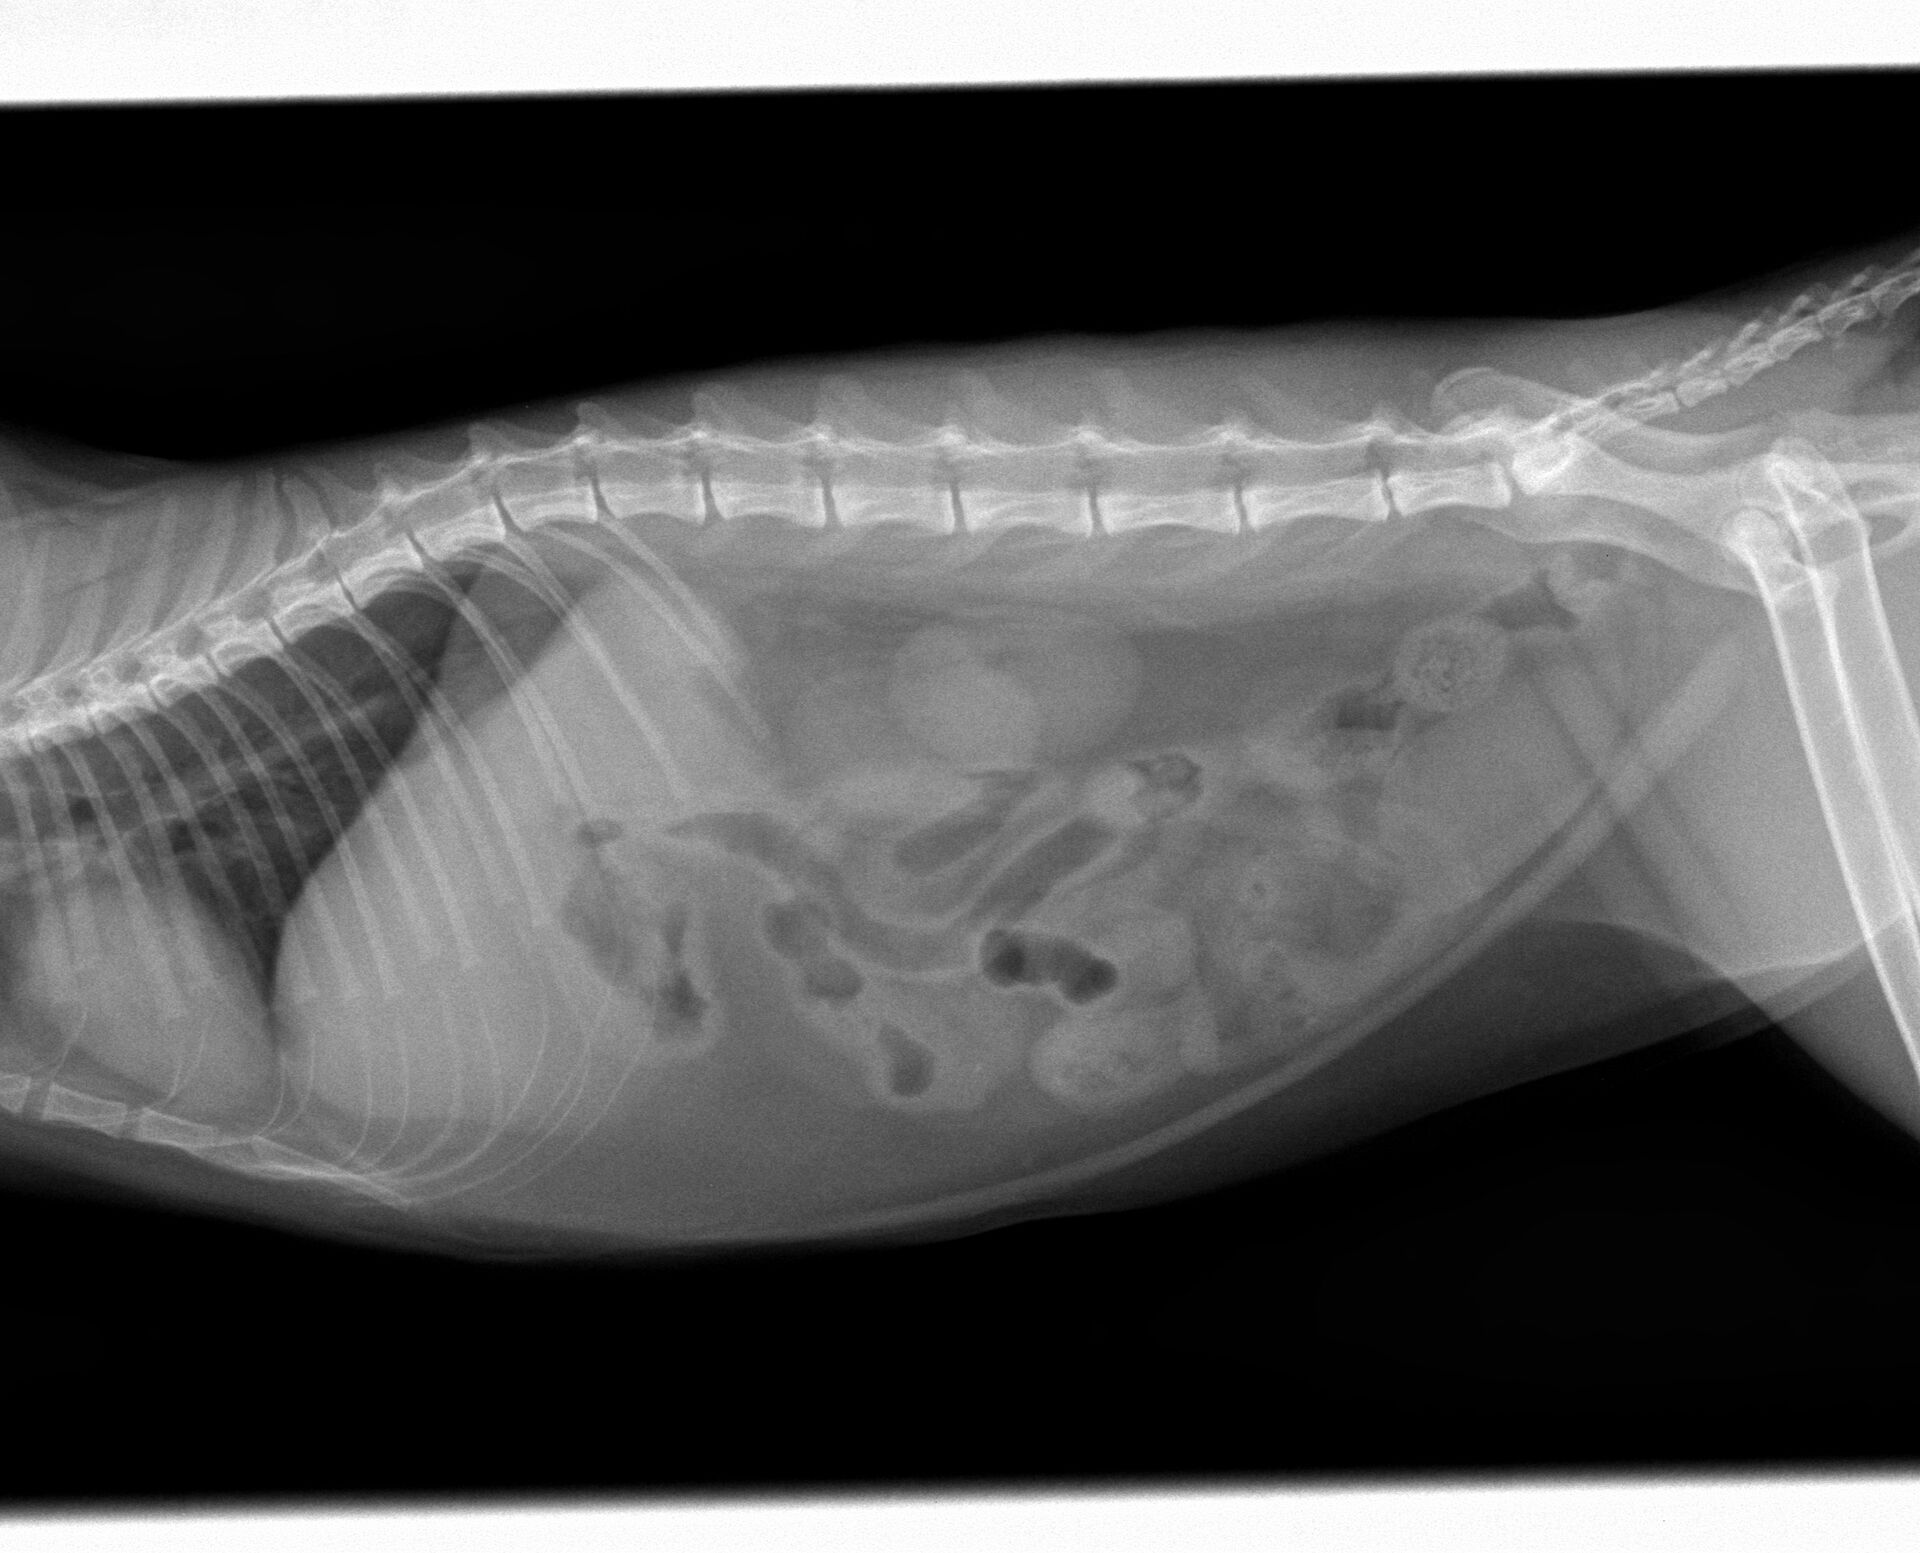

ある日突然食欲がなくなり、定期的に嘔吐するようになったとのことで来院しました。診察したところ、39度の微熱がある以外は脱水もなく、お腹を痛がったり、お腹に異物が触知されるということはありませんでした。また、飼い主さんに確認したところ、色々なものをかんだりすることがあるとのことでしたので、レントゲン撮影を行いました。その結果は特に異常は認められませんでした。